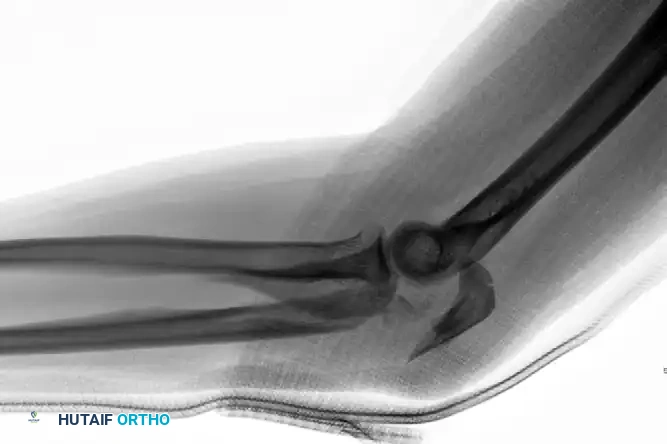

Preoperative Transolecranon Fracture-Dislocation:

Fixation with Lag Screws and Plate Spanning Entire Injury (AP View):

Fixation with Lag Screws and Plate Spanning Entire Injury (Lateral View):

Fixation with Lag Screws and Plate Spanning Entire Injury (Oblique View):

Anterior (Transolecranon) Fracture-Dislocations

In an anterior transolecranon fracture-dislocation, the mechanism involves the distal humerus imploding through the olecranon. This results in an anterior ulnohumeral dislocation. Crucially, in a true transolecranon injury, the proximal radioulnar joint (PRUJ) remains anatomically preserved, and the collateral ligaments (MCL and LCL) are typically intact.

These injuries vary in complexity, often presenting with extensive comminution and coronoid involvement. The routine treatment protocol demands anatomical reconstruction of the greater sigmoid notch articular surface followed by rigid plate fixation. The coronoid must be reduced and stabilized with lag screws first, followed by provisional articular reduction, and finally, a robust plate spanning the entire zone of injury.